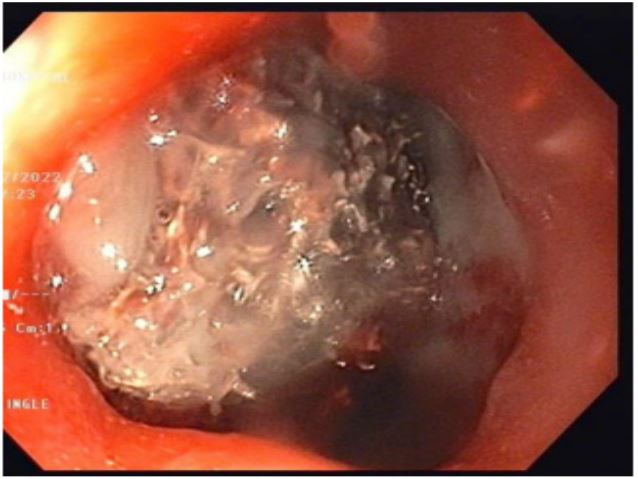

Case capsule 1

A 59-year-old man has complained of pus and mucus discharge from the anal region, as well as intermittent fever episodes, for the past two years. Three years ago, he developed symptoms of per rectal bleeding and was diagnosed with Carcinoma rectum, for which he received three cycles of neoadjuvant radiotherapy followed by laparoscopic anterior resection with a defuncting descending colostomy. He was discharged on post-operative day 8, with no issues reported. Adjuvant Chemotherapy was administered in 13 cycles. After 6 months of surgery, a CT abdomen was performed, which showed post-op changes in the pelvis with Pelvic peritoneal fat stranding and widening of the presacral space. He was having repeated episodes of fever with chills and pus discharge per anus that were resolved with IV antibiotics. After 6 months, an MRI of the pelvis revealed a significant collection of size 9.1 x 5.2 x 8.8 cm with air loculi at the presacral area-most likely a controlled leak (Figure 2). The conservative approach was continued for another six weeks, during which an intermittent fever with mucus and pus discharge from the anal region persisted. A colonoscopy was performed, which showed the cavity and confirmed the findings (Figure 4). Endovac sponges were sutured to RT and placed directly into the cavity with the help of a colonoscope after debriding and irrigating the cavity. After applying post-E-VAC therapy, the patient improved and had no fever after 48 hours. The procedure was repeated on an OPD basis four more times, with the endovac in place for five days each. At each session of endoscopy, there was a reduction in the size of the sponge used and considerable improvement in terms of the size of the cavity and the amount of slough (Figure 5). The cavity completely healed 10 weeks after E-VAC therapy, and the patient has been asymptomatic for the past 4 months. A CT scan showed complete resolution of the leak.

Figure 3: MRI pelvis showing collection in presacral area.

Figure 4: Colonoscopy showing post operative leak after anterior resection of ca rectum and placement of EVAC.